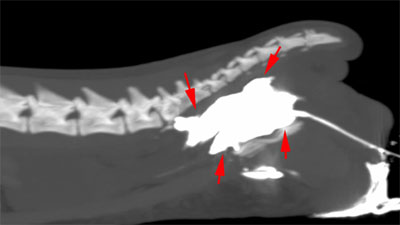

CT was used to identify the location of the rupture and a contrast was then injected into the urethra to test for leakage. The image below shows evidence of contrast (bright white) in an irregular pattern which has leaked out of the tract.

Soft tissue surgeon Francesco Gemignani explains “This type of injury is very challenging to manage. When we saw Salem there was already extensive soft tissue damage from urine leakage, and the location of the leak was challenging to access.